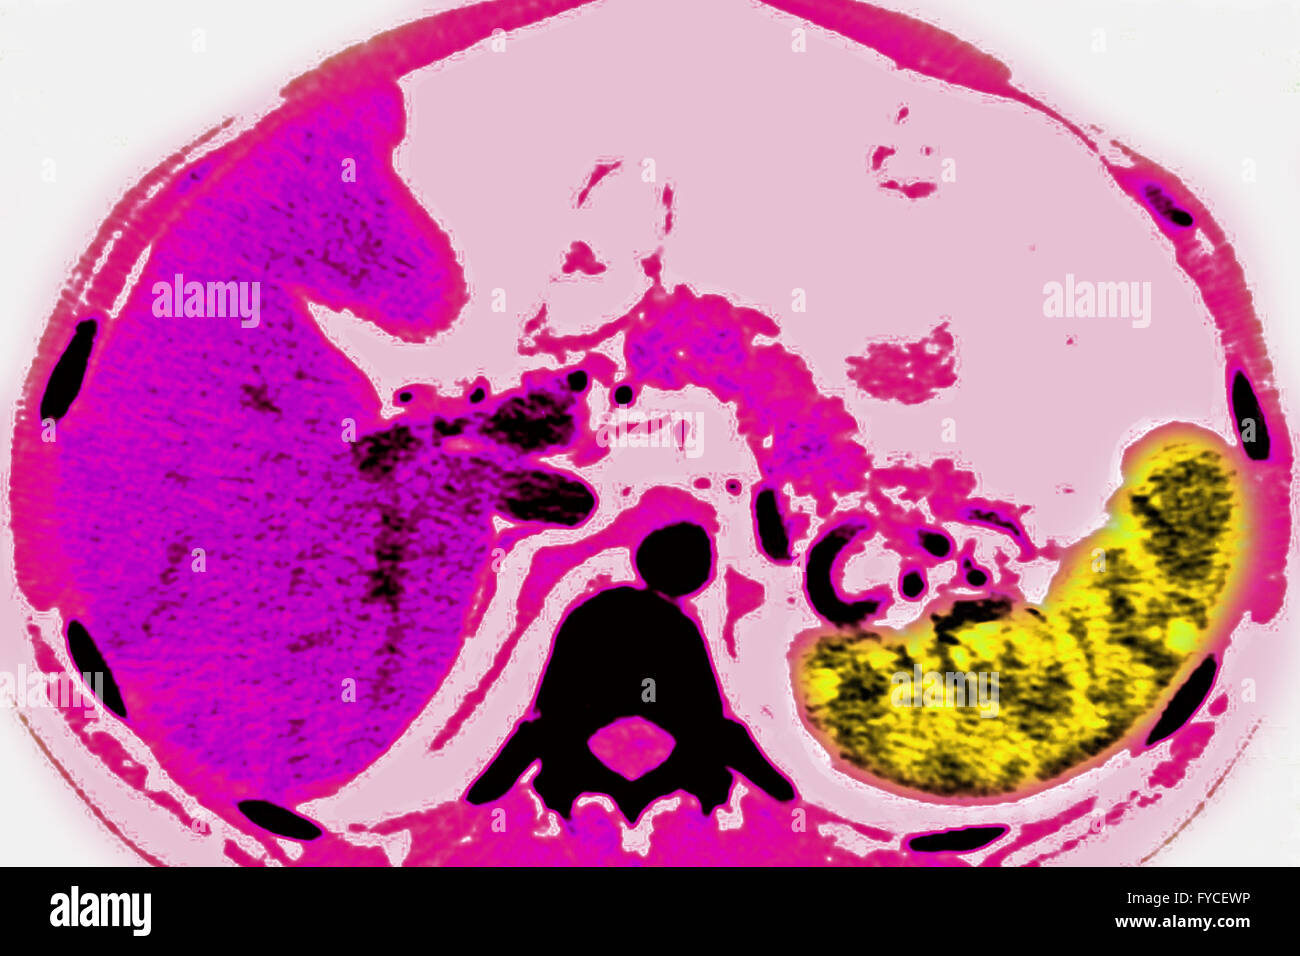

From www.alamy.com

ADENOPATHY SCAN Stock Photo Alamy Waxing And Waning Adenopathy Indolent lymphomas present with waxing and waning lymphadenopathy for many years, whereas aggressive lymphomas have specific b symptoms such as weight. Comparison with previous serial chest ct images showed a waxing and waning pattern compatible with aspiration bronchiolitis. Palpable supraclavicular, popliteal, and iliac nodes, and. Although the majority of indolent lymphomas (focusing on follicular lymphoma [fl]) have a prolonged waxing. Waxing And Waning Adenopathy.